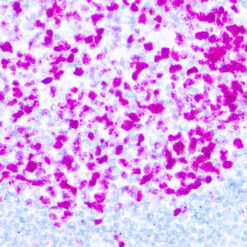

Leukocyte Common Antigen (LCA)/CD45

CD45R, also designated CD45 and PTPRC, has been identified as a transmembrane glycoprotein, broadly expressed among hematopoietic cells. Multiple isoforms of CD45R are distributed throughout the immune system according to cell type. These isoforms arise because of alternative splicing of exons 4, 5, and 6. The corresponding protein domains are characterized by the binding of monoclonal antibodies specific for CD45RA (exon 4), CD45RB (exon 5), CD45RC (exon 6) and CD45RO (exons 4 to 6 spliced out). The variation in these isoforms is localized to the extracellular domain of CD45R, while the intracellular domain is conserved. CD45R functions as a phosphor-tyrosine phosphatase. Antibody to CD45 is useful in differential diagnosis of lymphoid tumors from non-hematopoietic undifferentiated neoplasms.